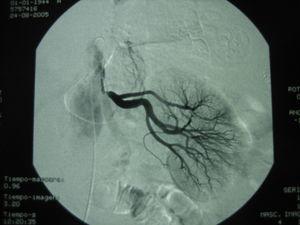

La presencia de enfermedad vascular generalizada, HTA y alcalosis metabólica inadecuada para su nivel de función renal hicieron sospechar la presencia de HTA reno-vascular, solicitándose arteriografía renal, y perfundiéndose 2000 cc en 24 horas de suero salino 0,9% para la prevención de la nefropatía por contraste, provocándose hipopotasemia (2,9 meq/l) si repercusión electrocardiográfica. En la arteriografía se detectaron estenosis de ambas arterias renales (fig. 1), corrigiéndose mediante angioplastia y stent.

Figura 1.